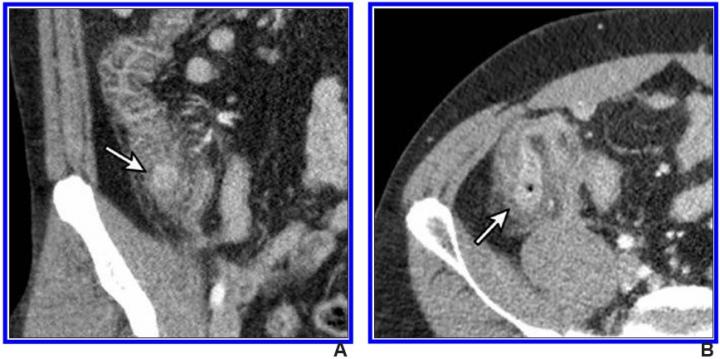

image: IV contrast-enhanced 2-mSv 4-mm-thick transverse and coronal (b) CT images show inflamed diverticula (arrows), segmental colonic wall thickening, and adjacent pericolic fat stranding.